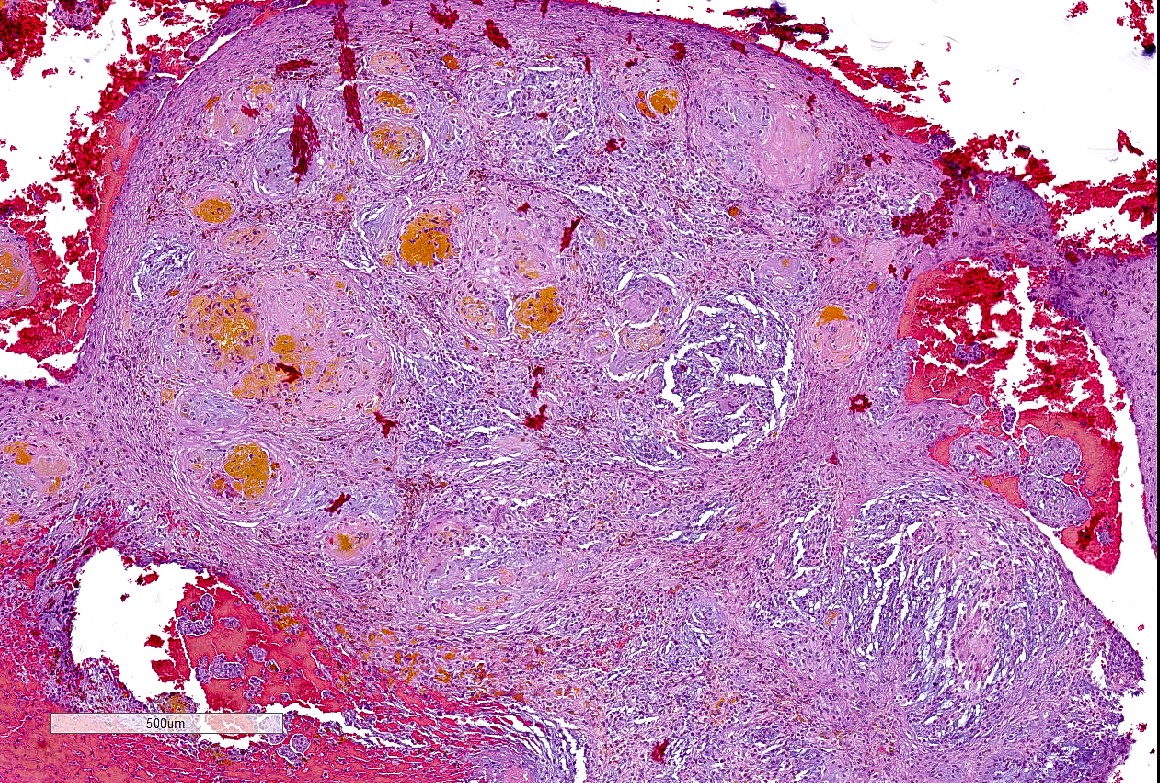

Microscopic (histologic) description

- Well demarcated tumor, often entrapped within skeletal muscle and frequently multilobulated (Am J Surg Pathol 2018;42:1297, Head Neck Pathol 2015;9:315)

- Stromal background may be hyalinized or demonstrate mucoid, myxoid or chondromyxoid areas

- Cords, strands or sheets of oval, round, fusiform or polygonal bland cells, sometimes arranged in a reticular / net-like or globoid pattern (Am J Surg Pathol 2018;42:1297)

- Myxoglobulosis-like changes have been noted (Virchows Arch 2003;442:302)

- May focally demonstrate fine calcifications, cellular atypia, necrosis, multinucleated giant cells (Am J Surg Pathol 2018;42:1297, Head Neck Pathol 2015;9:315, Oral Surg Oral Med Oral Pathol Oral Radiol Endod 1996;82:417)

- Cystic, slit-like spaces or hemorrhagic areas often noted (Head Neck Pathol 2014;8:329)

- Mitotic figures not seen (Head Neck Pathol 2015;9:315)

Microscopic (histologic) images